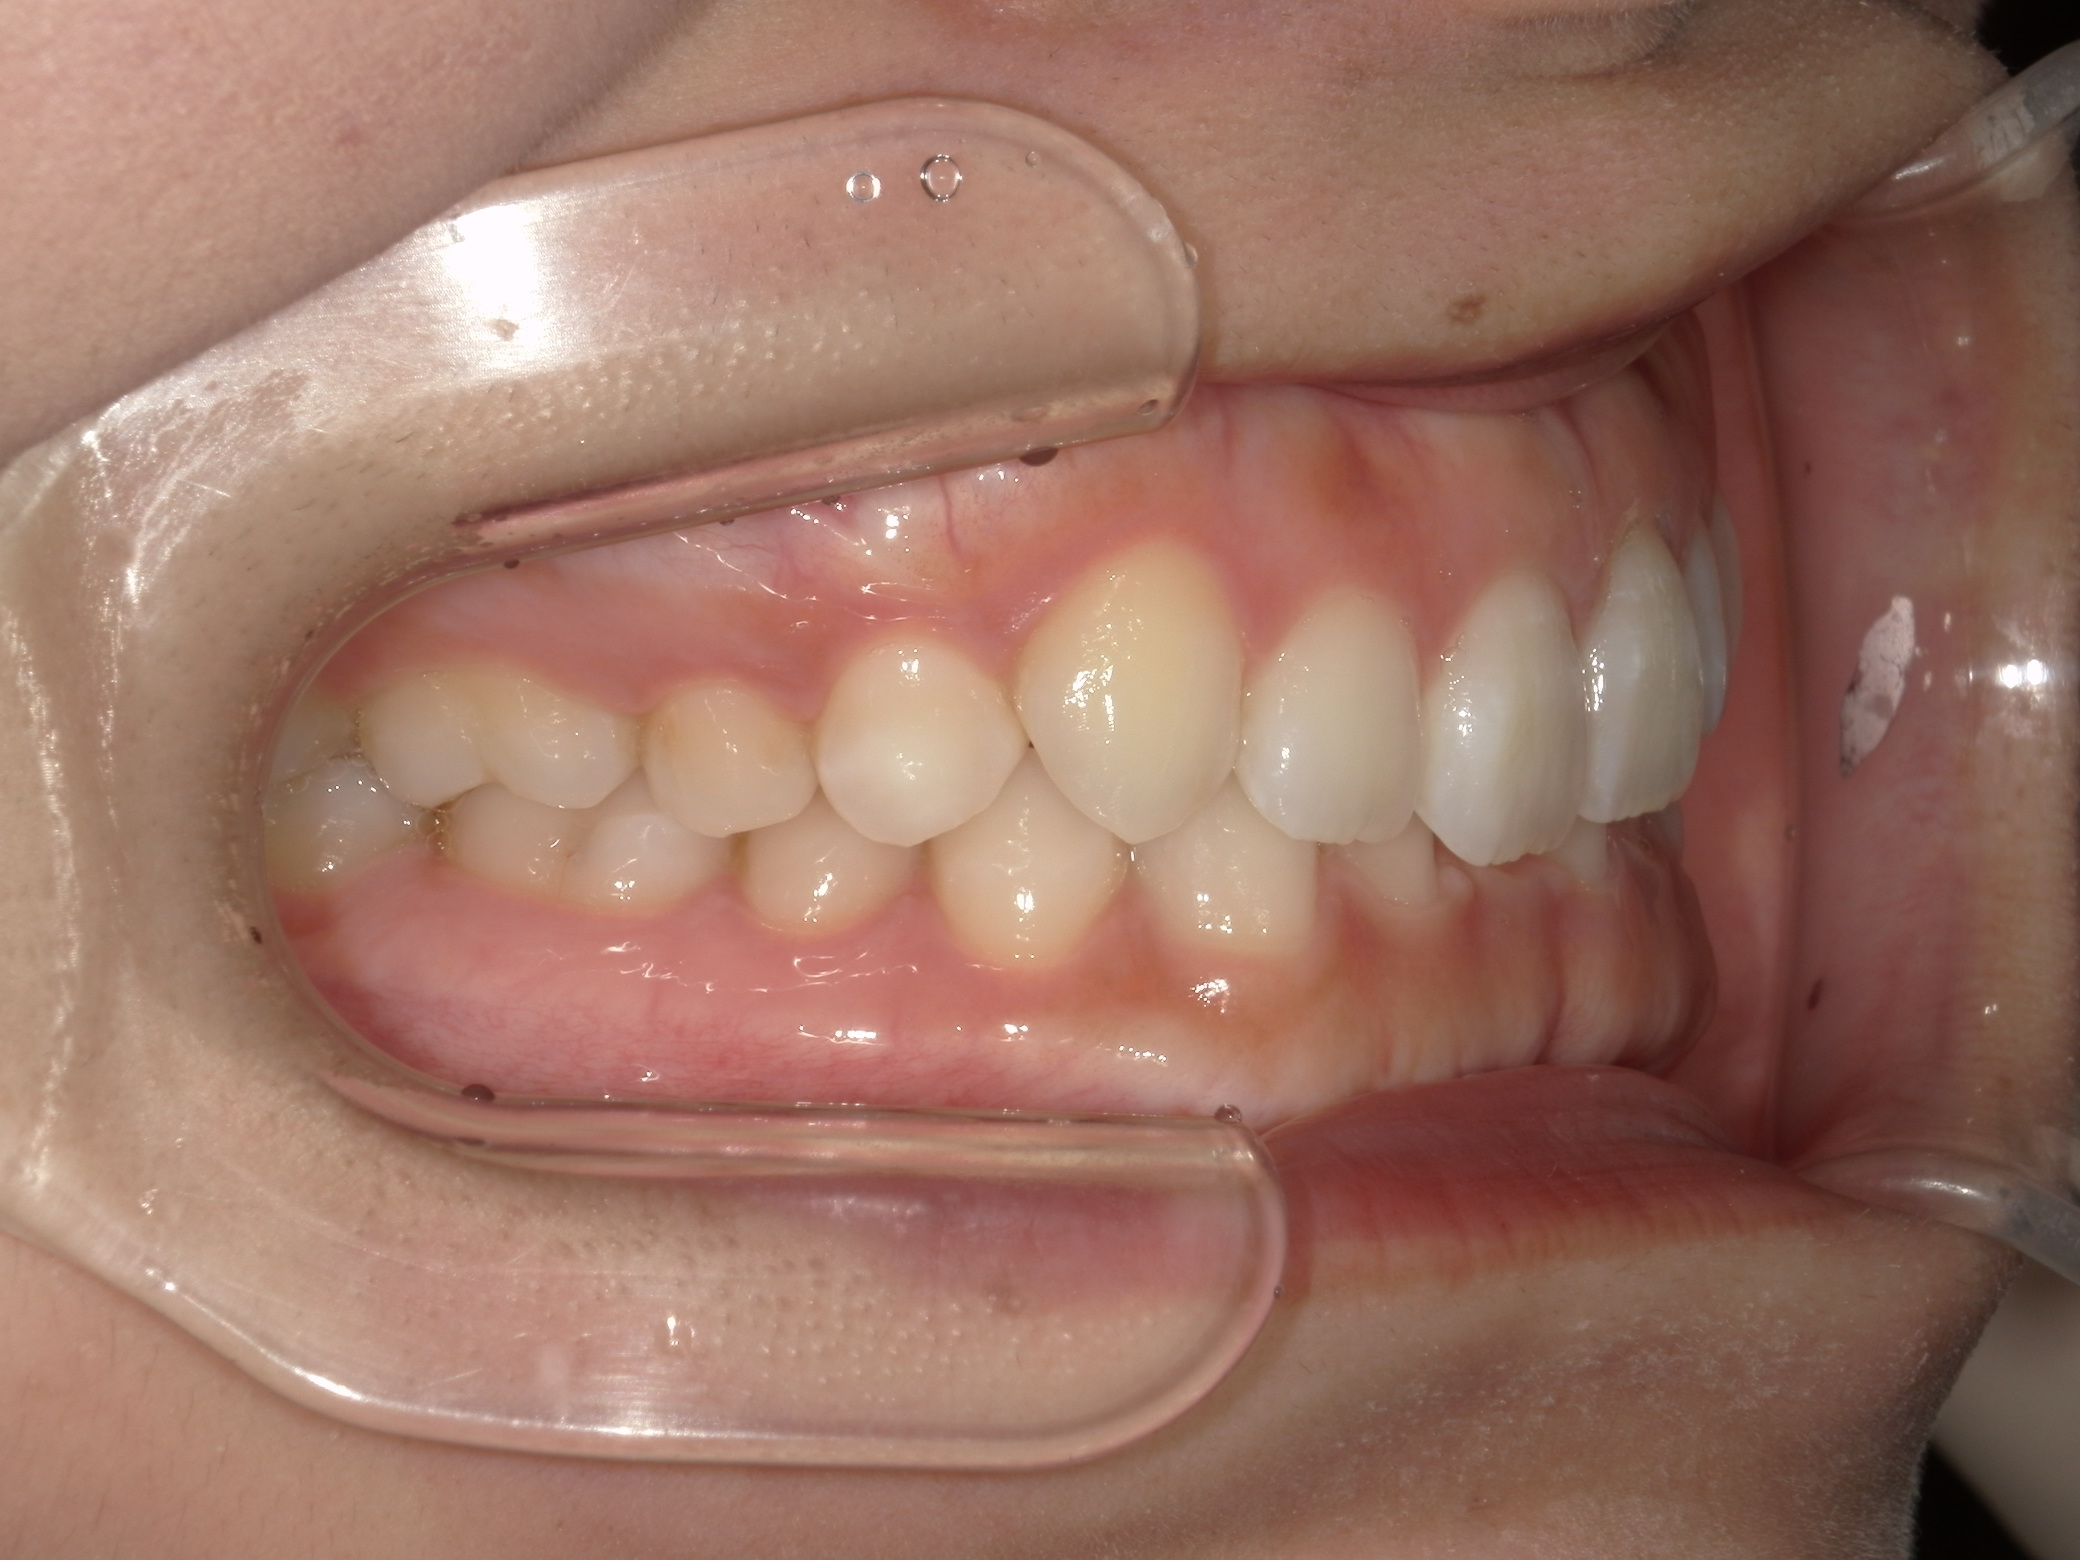

治療前の横からの歯並び

-